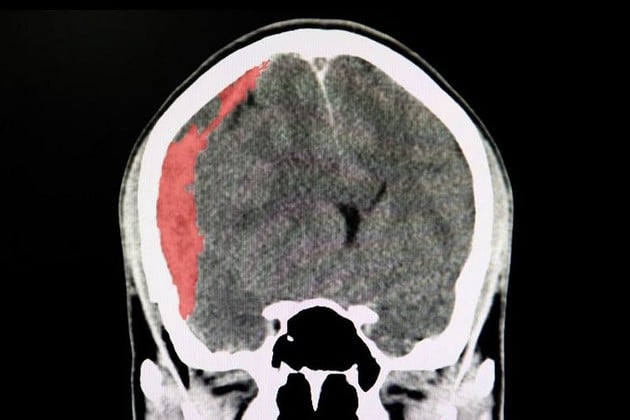

El hematoma subdural crónico se da entre la duramadre y el cerebro, y se pueden presentar por traumatismos de cráneo, algunos banales o por una desaceleración brusca, y se presentan en la parte externa del cerebro muchas veces en pacientes anticoagulados o antiagregados.

En sí son como pequeñas venas que sufren una ruptura en la superficie del cerebro, pasa desapercibido y el hematoma con el tiempo progresa por la propiedad oncótica de la sangre que atrae líquido.